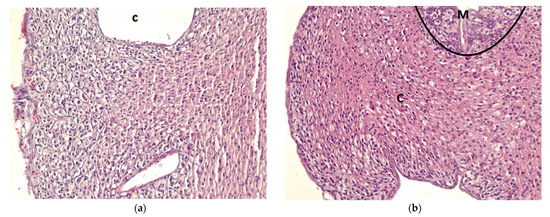

3.2. Clinical Observation—Preliminary Data